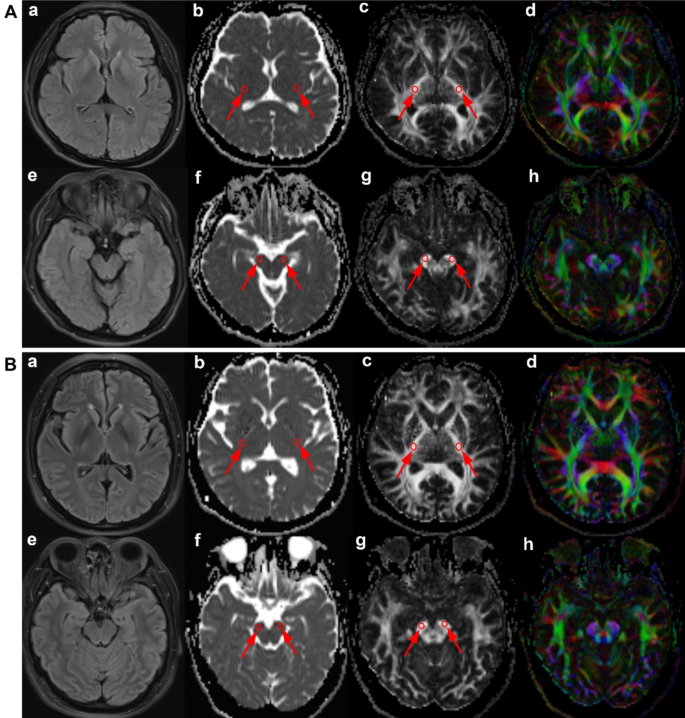

The original DTI maps were transmitted to post-processing workstation with Neuro 3D software to generate the MD and FA maps. Regions of interest (ROIs) were selected on the FA and MD maps. These ROIs were manually delineated on axial slices of the posterior limb of internal capsule and the cerebral peduncle along the left and right corticospinal tracts respectively. We calculated MD and FA values for bilateral ROIs. In clinical practice, we found that ALS patients typically exhibit symmetrical lesions on both sides in CST in T2FLAIR sequence of MRI. Using average measurements from both sides could reduce errors. Then, the average value of the bilateral ROIs at the same slice was calculated. Capsule-FA, Peduncle-FA, Capsule-MD and Peduncle-MD values were derived, representing the DTI parameters at the levels of the internal capsule and the cerebral peduncle. Figure 1A,B demonstrated T2FLAIR, MD, FA and FA pseudo-color maps of healthy control and ALS. A total of two blinded, board-certified radiologists performed the image analyses.

(A) Upper row: T2FLAIR (a), MD (b), FA (c) and FA peudo-color (d) maps of healthy control on the internal capsule level; Low row: T2FLAIR (e), MD (f), FA (g) and FA peudo-color (h) maps of healthy control on the cerebral peduncle level. (B) Upper row: T2FLAIR (a), MD (b), FA (c) and FA peudo-color (d) maps of patient with ALS on the internal capsule level; Low row: T2FLAIR (e), MD (f), FA (g) and FA peudo-color (h) maps of patient with ALS on the cerebral peduncle level.